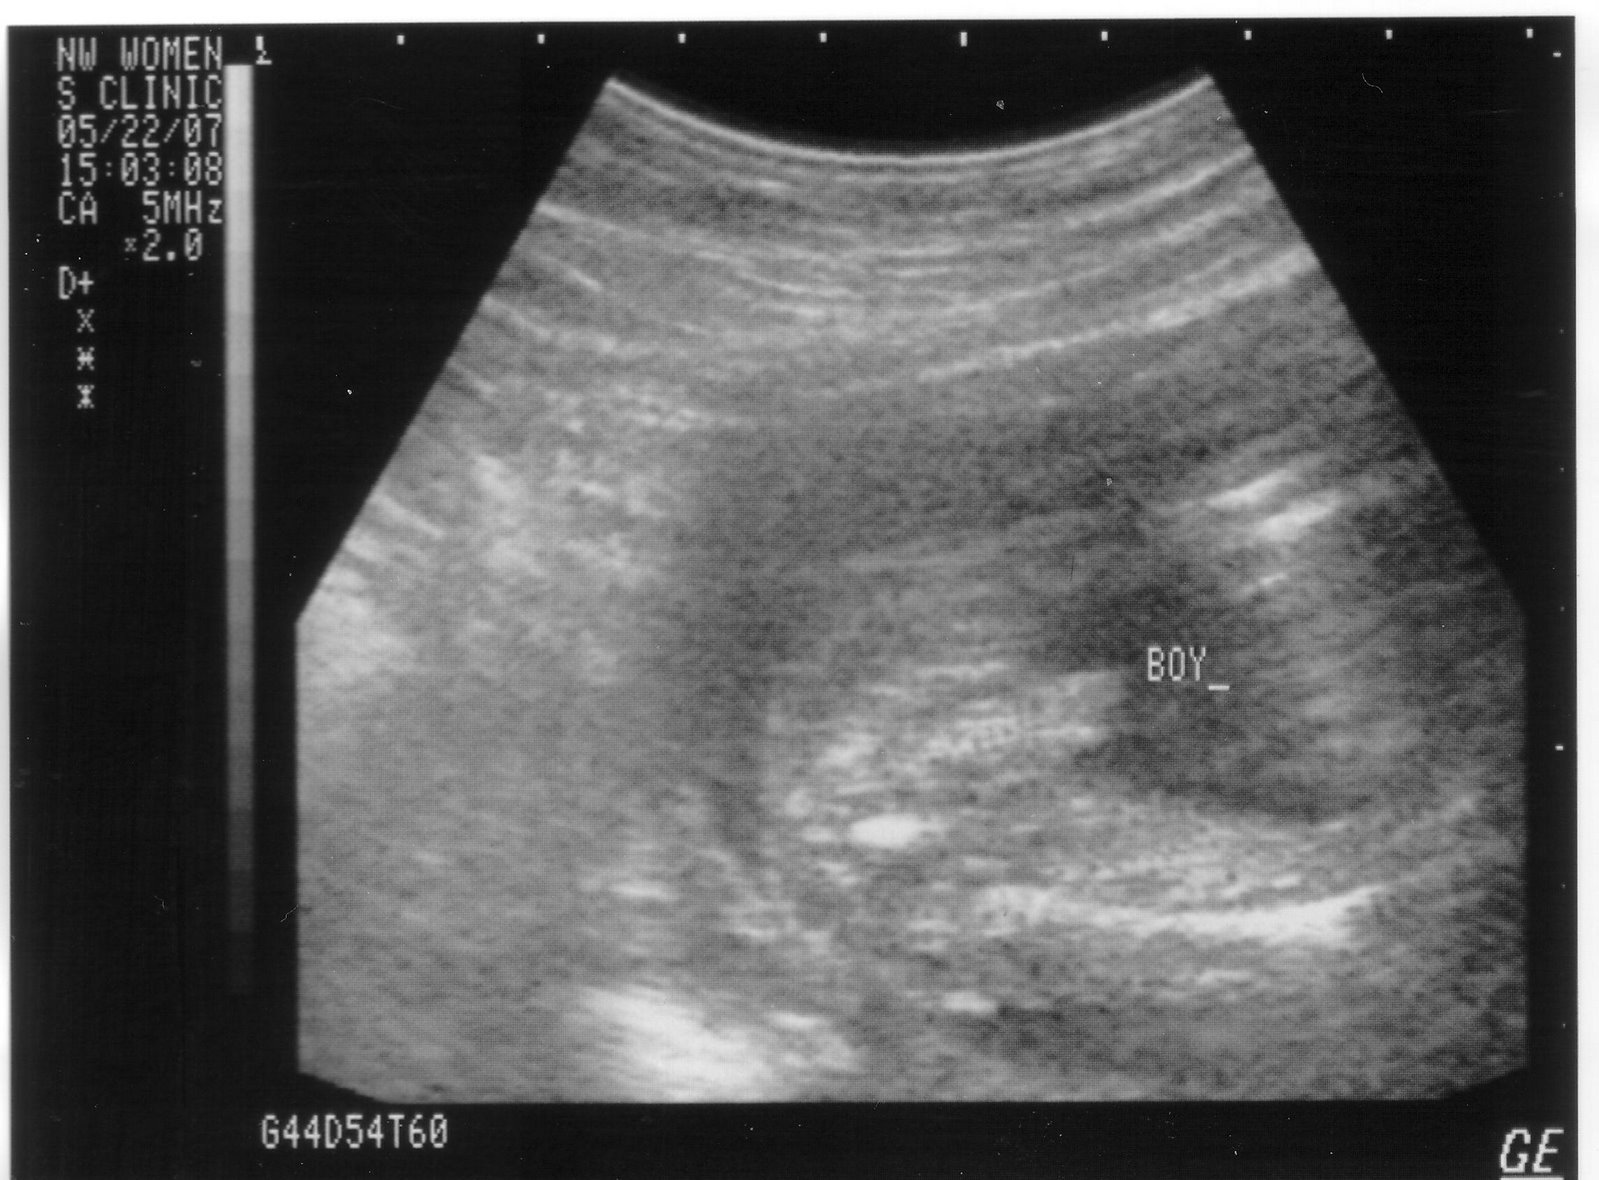

The new Momma is doing just fine and 'growing' into her new role as mother. We are enjoying thinking about Pooter and wondering if we will be having a boy or girl. We find out June 12th!